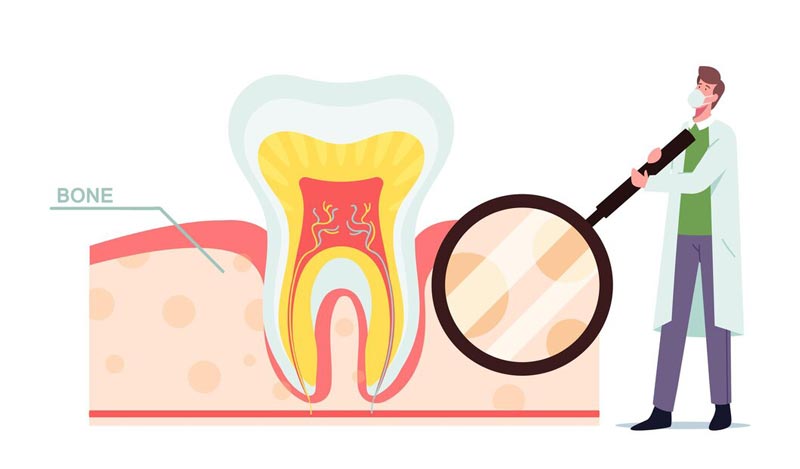

درمان ریشه دندان به معنای خارج کردن عصب یک دندان، تمیز کردن و شکل دادن به فضای کانال است و در آخر نیز جهت ممانعت از ورود میکروب و باکتری به عصب دندان باید دندان را پر کنند. درمان ریشه دندان به این جهت انجام می شود که دندان را هر چند بدون عصب زنده داخل دهان داشته باشیم و در کنار آن نیز در زمان خوردن درد نداشته باشیم. دندانپزشک متخصص در کلینیک دندانپزشکی تریدنتال می تواند بهترین خدمات را در این زمینه به شما ارائه دهد. همچنین باقی ماندن دندان داخل دهان باعث حفظ زیبایی و ظاهر بیمار نیز می گردد. درمان ریشه دندان معمولاً نیازمند یک یا دو جلسه ملاقات با پزشک می باشد، اما در بعضی موارد ممکن است به علت سختی کار یک جلسه دیگر نیز به دوره درمان ریشه دندان اضافه شود.

درمان ریشه دندان زمانی لازم می شود که دکتر درمان ریشه تشخیص دهد ناحیه نرم بافت دندان دچار عفونت شده است. این عفونت منجر به پوسیدگی دندان می گردد. در این مواقع عکس رادیولوژی توسط پزشک تجویز می شود و عفونت ها و وضعیت دندان بیمار کامل بررسی می شود، زیرا این عکس دارای اشعه ایکس می باشد و وضعیت کلی دندان و مشکلات احتمالی را نیز می توان از روی آن تشخیص داد. علائم تشکیل عفونت دهان را می توان از روی لق شدگی دندان، درد هنگام خوردن و آشامیدن به خصوص مواد سرد و گرم و … تشخیص داد. برای درمان تخصصی ریشه دندان در تهران به کلینیک دندانپزشکی تریدنتال مراجعه و از مشاوره با متخصص ریشه بهره مند شوید.

در صورتی که عفونت دهان پیشرفت کند، دیگر این علائم را شاهد نیستیم، زیرا عفونت به ریشه دندان رسیده و عصب دندان از بین می رود. پس از این مشکلات دیگری متوجه دندان می شوند، از جمله آن ها می توان به موارد زیر اشاره کرد: ورم لثه اطراف دندان آسیب دیده، ترشح چرک از دندان، ورم صورت، درد در زمان جویدن و تیرگی دندان. درد عصب کشی دندان تقریبا زیاد است، اما دردی که به هنگام درمان ریشه مواجه فرد است، کمتر از درد درمان در هنگام پر کردن دندان می باشد. اما این را هم باید مد نظر داشت که ممکن است بعد از درمان درد قابل توجهی را داشته باشیم.